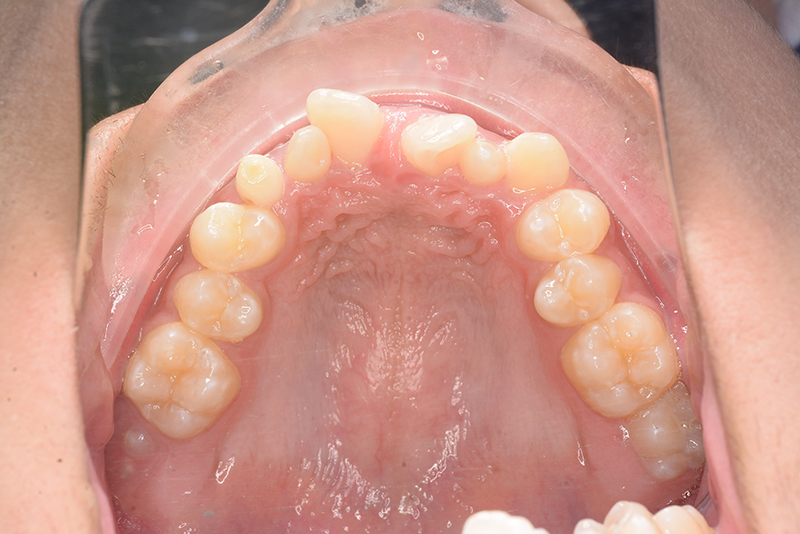

初診時

FP・IOP

主訴 すきっ歯 診断名 上顎右側犬歯先天欠如を伴うアングルⅡ級空隙歯列症例

初診時年齢 15歳5ヵ月 性別 動的治療期間 21ヵ月

口腔内所見 over jet 8.0mm、over bite 8.0mmで下顎歯列はスピー湾曲が強く、過蓋咬合、上突歯列、叢生歯列を呈しており、臼歯関係はⅡ級、左側7は鋏状咬合となっていた 。上顎両側2は矮小歯で上顎右側Cは晩期残存をしていた。また上顎歯列は空隙歯列を呈していた。